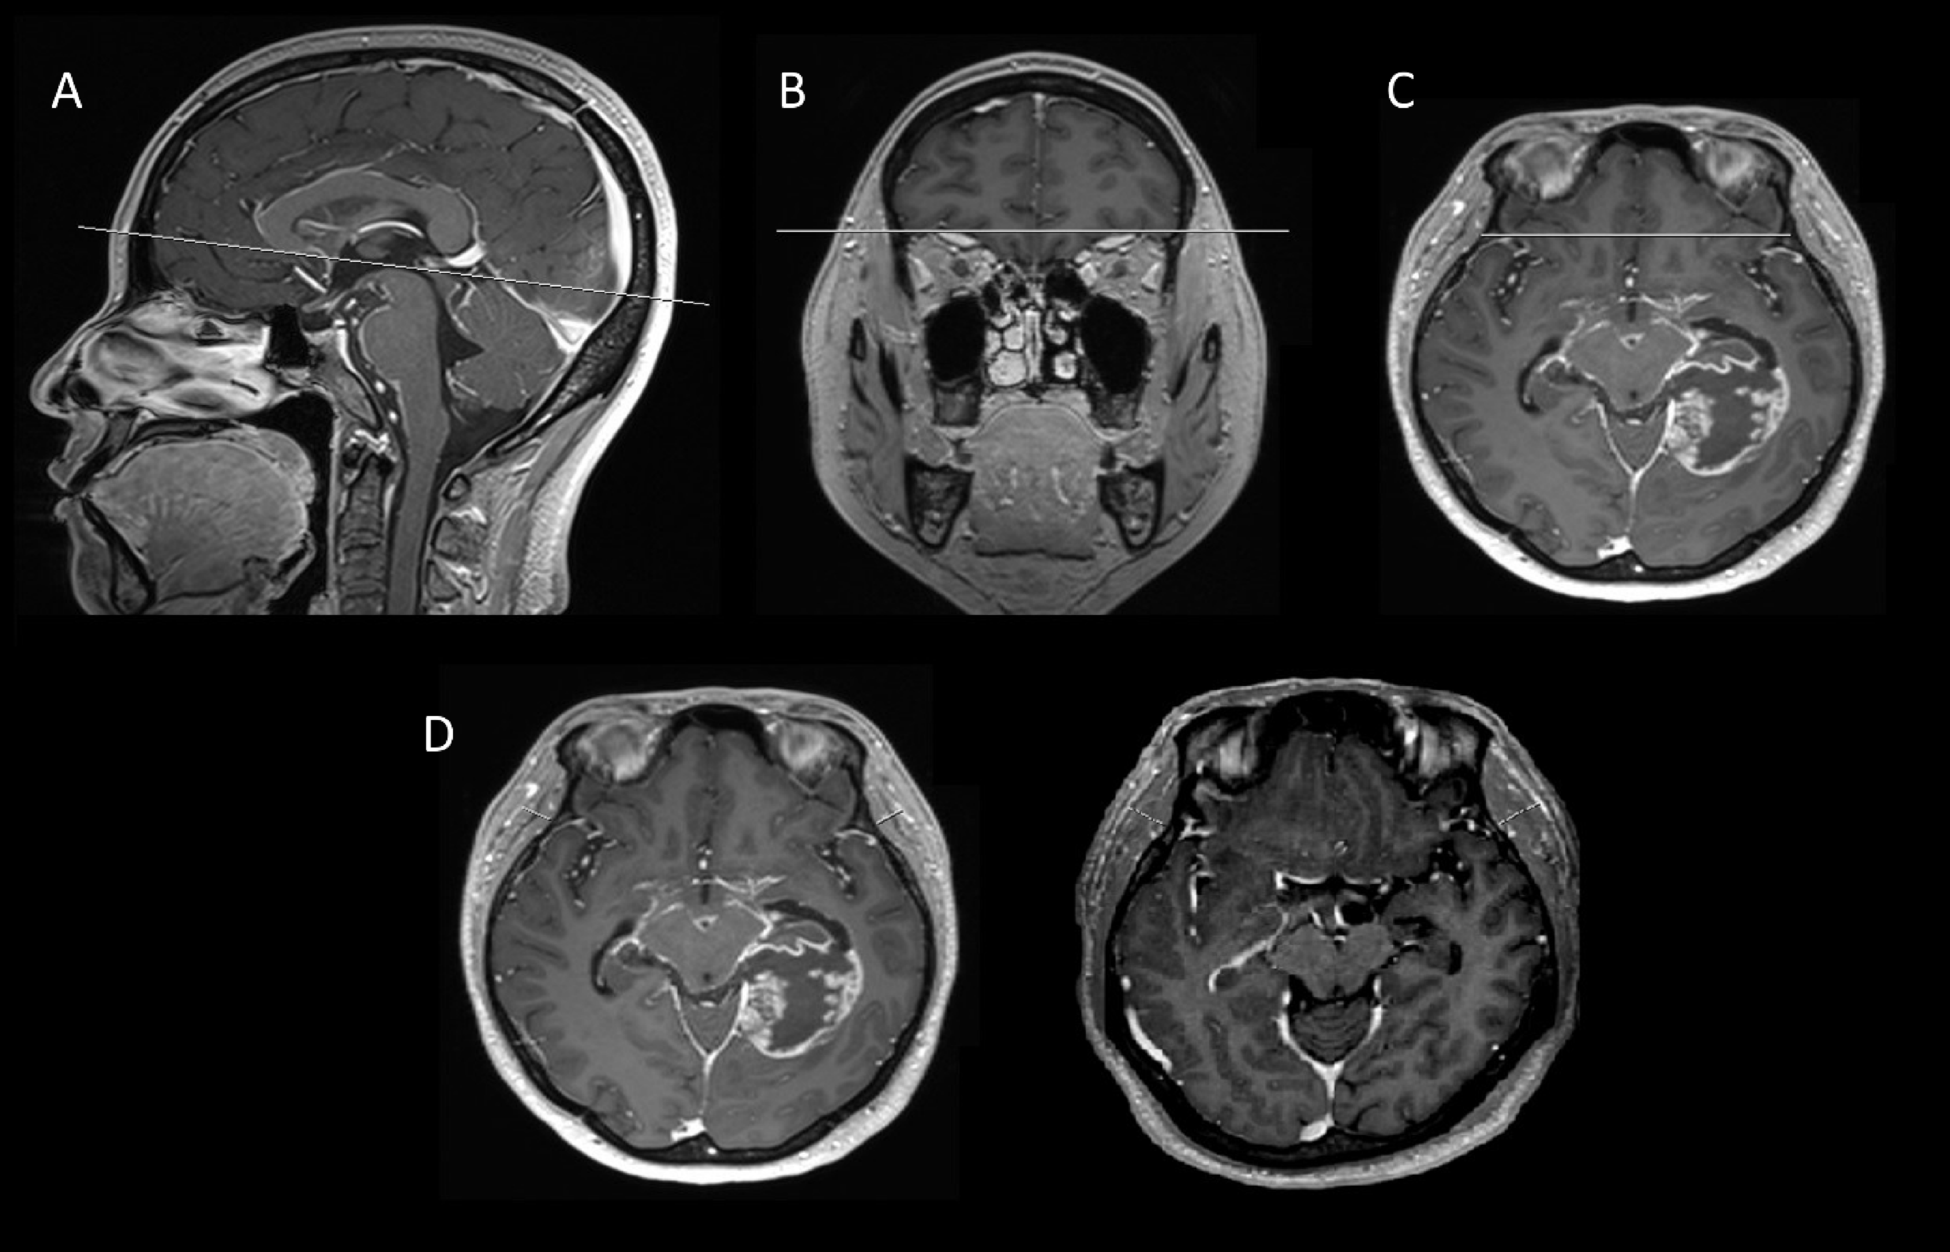

Fig. 4

From: Added prognostic value of temporal muscle thickness in glioblastoma with age-stratified analysis

Example of TMT measurements using 3D thin-Sect. (1 mm-thickness) contrast-enhanced T1-weighted MRI. (a–c) Axial images demonstrating MRI alignment for TMT acquisition. (d) A 55-year-old female with sarcopenia (left), a 76-year-old male without sarcopenia (right). TMT temporal muscle thickness, MRI magnetic resonance imaging.